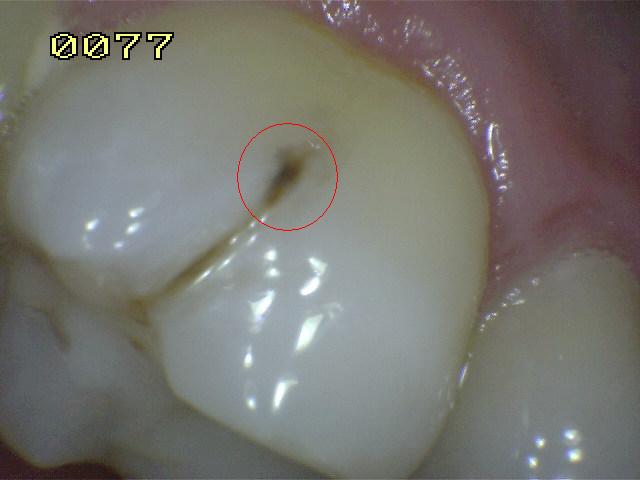

¿Determine los códigos pertinentes a cada imagen?

Click en el hipervínculo: Para comparar el resultado de su diagnóstico